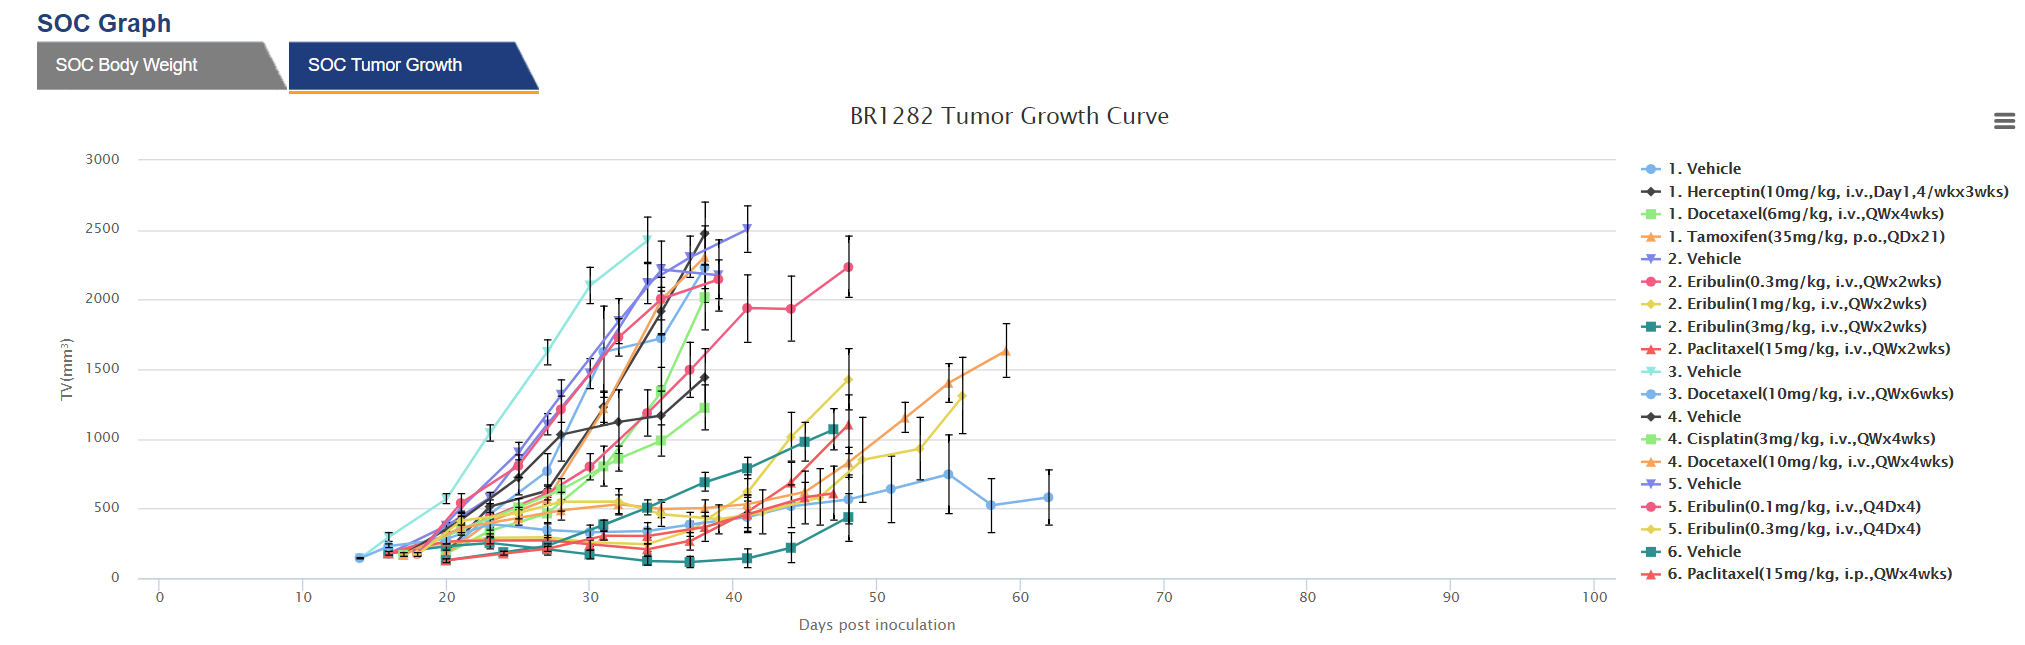

可搜索PDX模型数据库HuBase™中的大量特性鉴定数据包括:超过1,500个模型的RNAseq、超过680个模型的全外显子组测序、组织学、生长动力学以及SoC和研究性治疗数据。

登录并在我们可搜索的数据库内探索冠科生物具备完善表征的人源肿瘤异体移植模型。获取基因组、分子和表现型数据,包括肿瘤生长曲线、标准治疗反应、组织病理学数据的患者信息